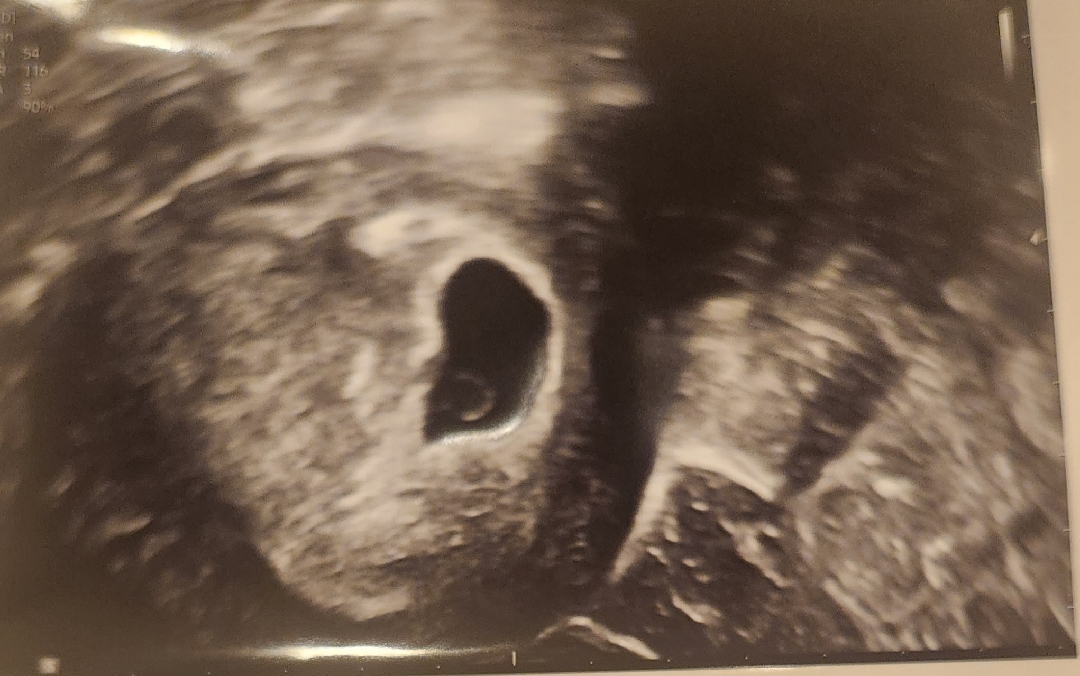

5주 3일차!

초음파 처음 보고 왔어요!! 아직 입덧도 하나도 없고.. 생리할때 생리통이 아주 약하게 있는 느낌이예요 예정일 6월 12일인데 비슷한 예정일이신 분들 증상 어떠신가요~~